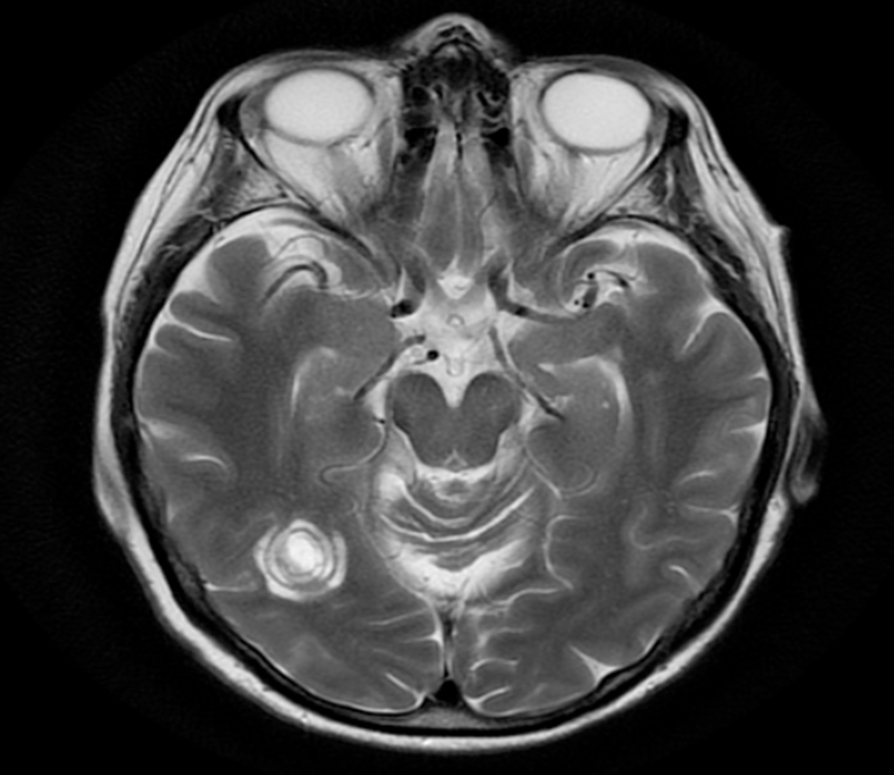

Paziente uomo con progressivi disturbi visivi. La RM encefalo mostra questa lesione:

Il reperto sarebbe più compatibile con la diagnosi di:

- Sindrome di Balò

- Sindrome di Devic

- SLA

- Pseudotumor cerebri

- Meningite tubercolare

La sindrome di Balò (Risposta esatta: A) è una forma rara di leucoencefalopatia caratterizzata da lesioni concentriche, che si presentano come anelli alternati di alta e bassa intensità in RM. Queste lesioni tipicamente colpiscono i giri longitudinali e periventricolari del cervello, e il loro aspetto è descritto come “anelli di cipolla”. L’aspetto concentrico delle lesioni è uno dei segni distintivi della sindrome di Balò, che può essere un fenomeno acuto o subacuto e spesso è associato a disturbi neurologici progressivi.